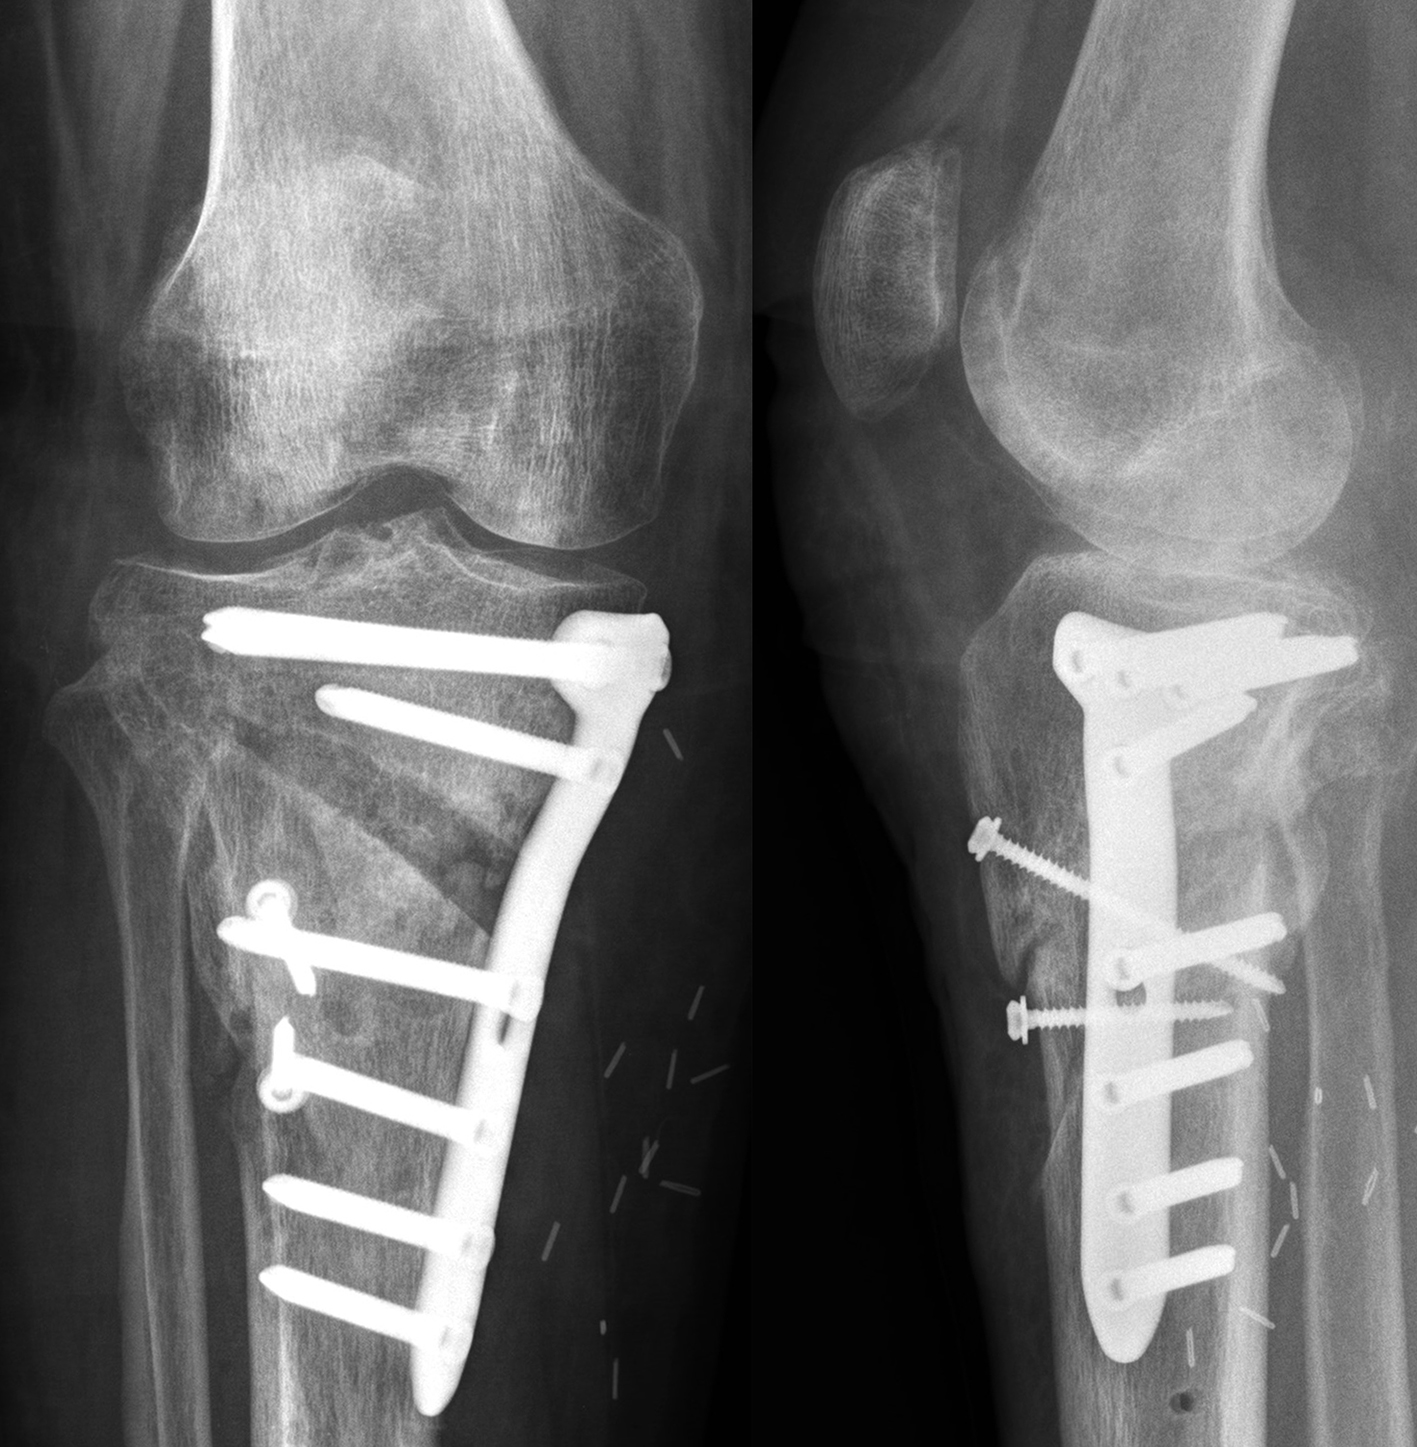

Not only does the new TomoFix Knee Osteotomy System contain a new MHT plate with more anatomical features, it also includes new osteotomy instrumentation intended to improve both surgical accuracy and procedural efficiency. The new instrumentation is compatible with the existing Standard and small TomoFix Medial High Tibia plates. Fig 4 shows a patient with post-traumatic deformity after a proximal tibial fracture (at the 6-week follow-up after open wedge HTO in descending technique and fixation with the TomoFix MHT anatomical plate).